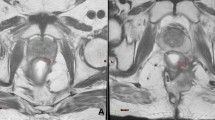

T2-weighted fast spin echo 2D-oblique images acquired on a transversal plan orthogonal to the tumour longitudinal axis were used for the radiomics analysis, in order to be consistent with the original experience reporting the model.

The GTV was firstly contoured by a radiation oncologist of the lower gastro intestinal malignancies department, and then an independent validation was performed by a senior radiation oncologist of the same department.